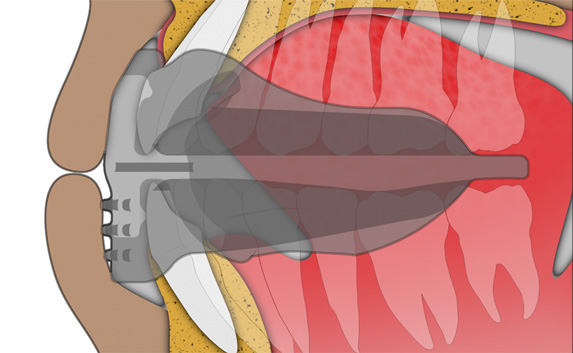

Establish nasal breathing and correct TMJ function

The Myosa® for TMJBDS® S3 is used in the third and final stage of treatment, when the patient's Breath Hold Time (BHT) has reached 45 seconds or more. The S3 is primarily designed to finalise the establishment of nasal breathing, while improving breathing and myofunctional disorders. The S3 can also serve as a transition appliance between the first and second phase of TMJBDS® treatment, involving arch development in combination with the Myobrace® appliances. It is for this reason that the S3 is a derivative of the Myobrace®A1 appliance.